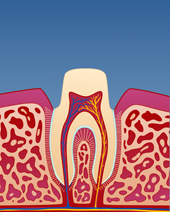

figur III

Et detaljbilde viser rette, slitte kanter på tennene.